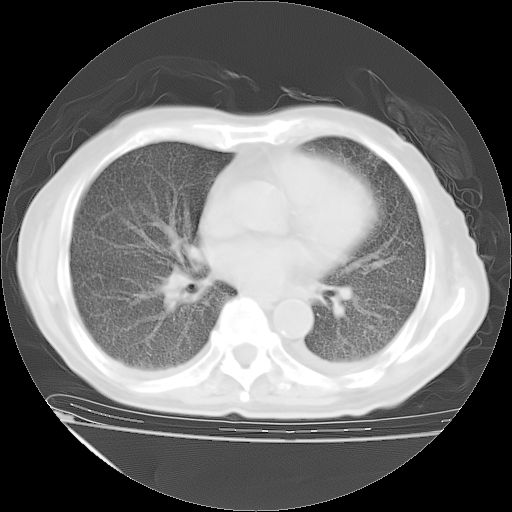

仔细阅读病史资料和CT,我觉得两肺粟粒结核要高度怀疑。

昨天我们影像科主任说由于12天前在齐鲁医院的肺部CT无确切改变,所以不考虑肺结核。

但我们感染病科老主任认为粟粒性肺结核可能性大。

今天带四次肺CT片到市医院,影像科4~5个主任都认为不考虑粟粒性肺结核。主要理由是在3月19日、4月2日、4月27日的CT片没有见到确切异常(肺结核)影像。影像科主任们建议找呼吸内科主任,呼吸内科主任认为首先考虑粟粒性肺结核。

甲强龙80mg/日+抗结核治疗(异烟肼+利福霉素+乙胺丁醇)10天。复查肺部CT。

治疗10天肺部CT